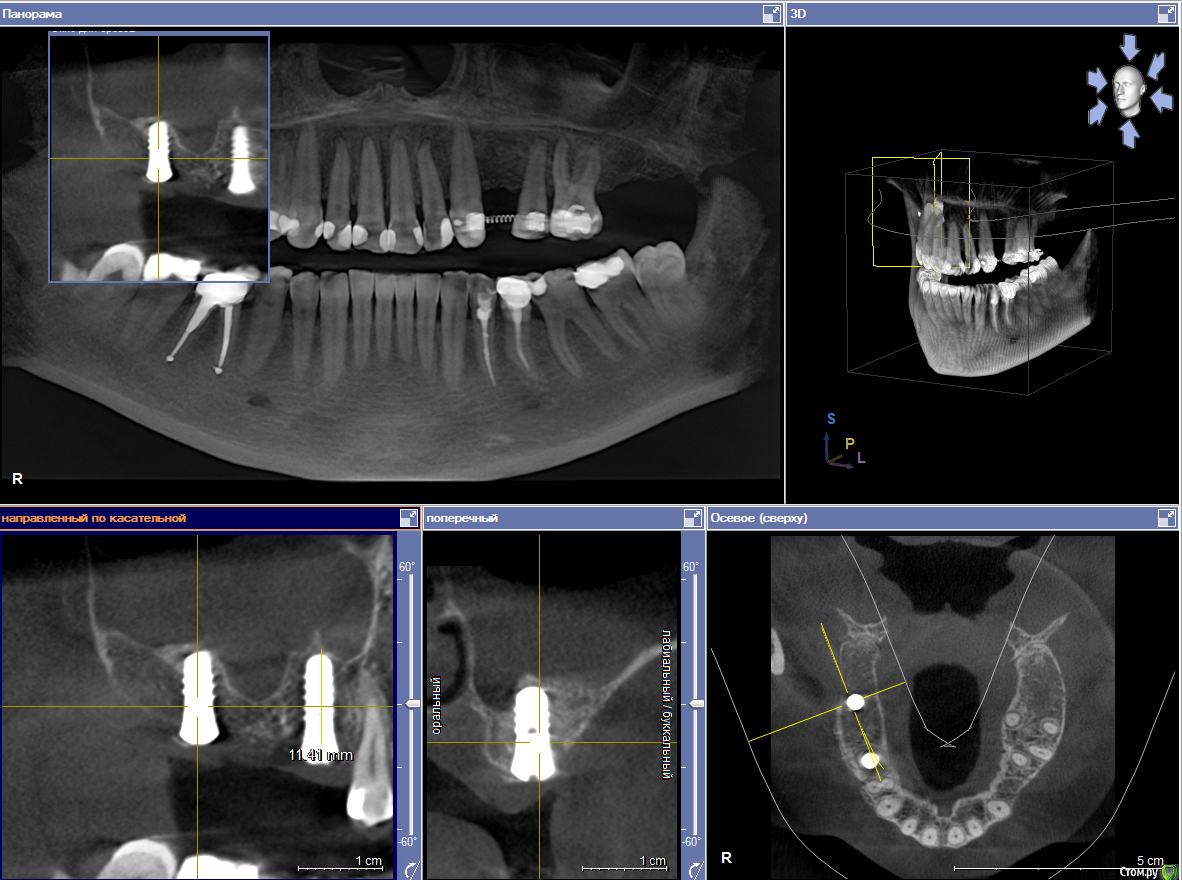

Закрытый синус 15,17 з

Пациентка пришла с целью восстановления отсутствующих 15,16,17,24,27 з.

Из анамнеза - хронический двухсторонний синусит, соответствующие зубы удалены более 5-ти лет назад, тетрациклиновые зубы ( от изменения цвета отказалась ).

Хирургический план :  консервативное лечение у ЛОР специалистов

1) имплантация в позиции 15,17 з с закрытым синусом и незначительной НКР

2) коррекция слизистой в области 1-го сегм

3) имплантация с ССТ в позиции 24 з ( после дистализации 25,26 з), в области 27 з на момент  операции был гнойный синусит, отложили